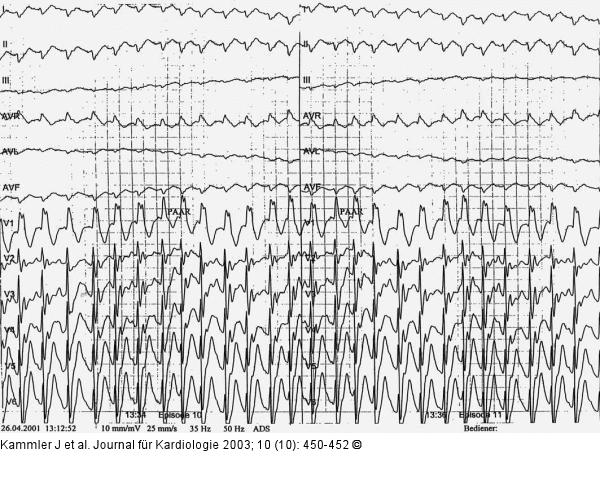

Abbildung 1: Ventrikuläre Tachykardie Ventrikuläre Tachykardie während Ergometrie. Papiervorschub 25 mm/s |

Ventrikuläre Tachykardie während Ergometrie. Papiervorschub 25 mm/s |